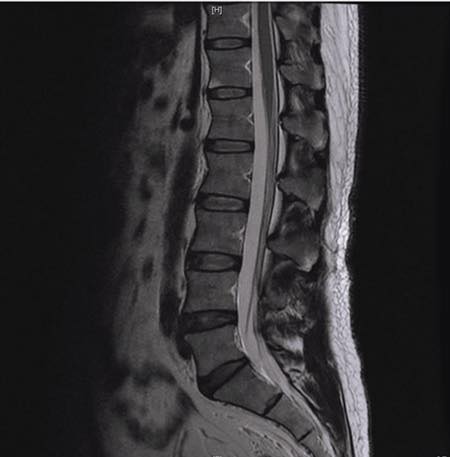

個案為台北市五十多歲的林先生,長期偏頭痛、頭暈、焦慮、恐慌、胸悶、睡眠障礙、腰背痠痛、胃酸逆流、脹氣,拿了2019/5拍的頸椎的MRI 與腰椎MRI來看,發現腰椎完全沒有任何問題!但就是很長期的腰酸背痛,頸椎也只有看到一點輕微的壓迫,可是症狀怎麼會那麼嚴重!!